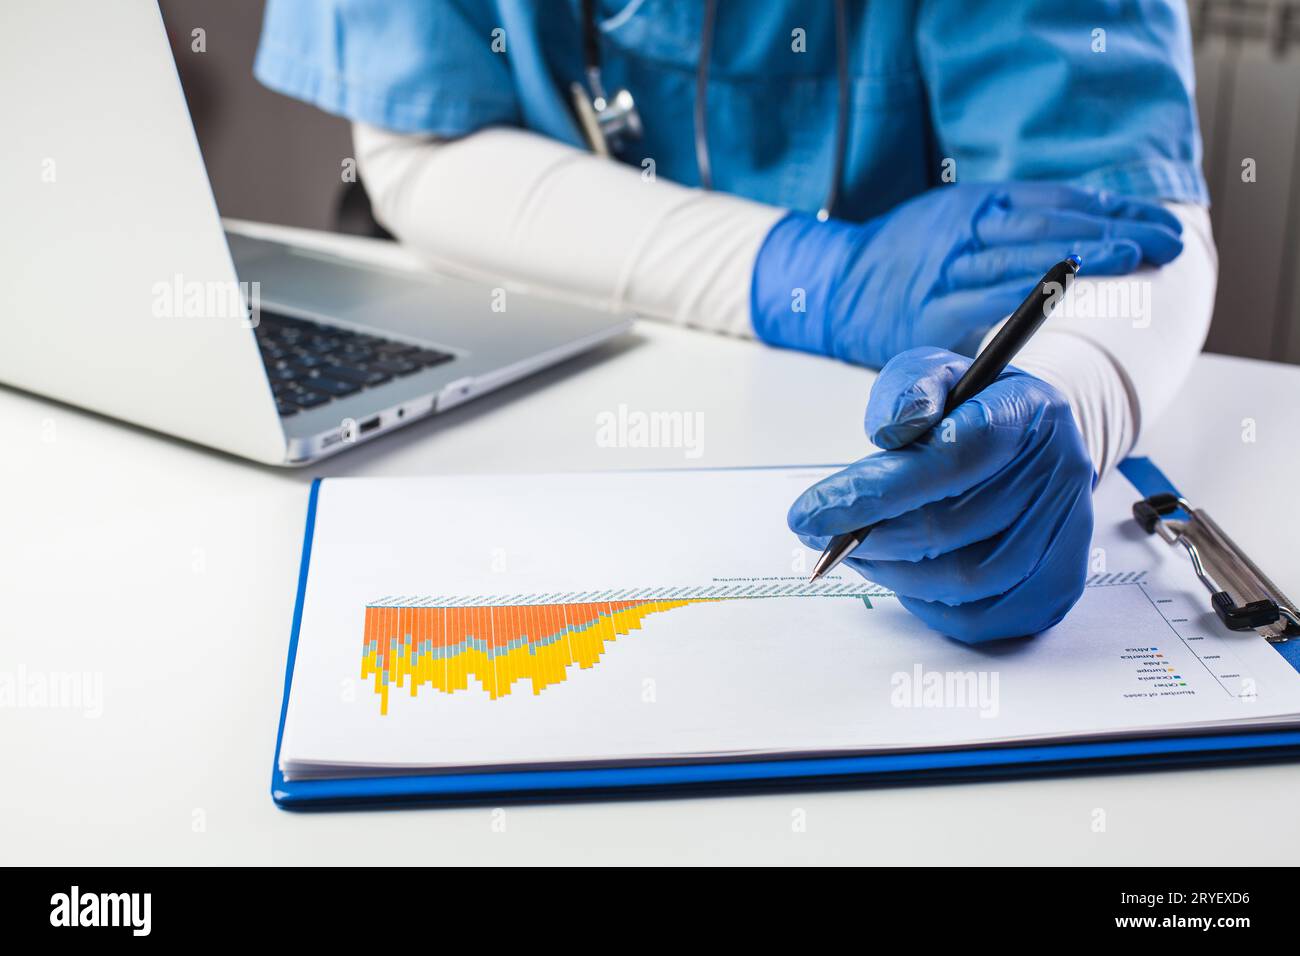

Doctor wearing protective gloves analyzing COVID-19 info data Stock Photohttps://www.alamy.com/image-license-details/?v=1https://www.alamy.com/doctor-wearing-protective-gloves-analyzing-covid-19-info-data-image567655570.html

Doctor wearing protective gloves analyzing COVID-19 info data Stock Photohttps://www.alamy.com/image-license-details/?v=1https://www.alamy.com/doctor-wearing-protective-gloves-analyzing-covid-19-info-data-image567655570.htmlRF2RYEXD6–Doctor wearing protective gloves analyzing COVID-19 info data